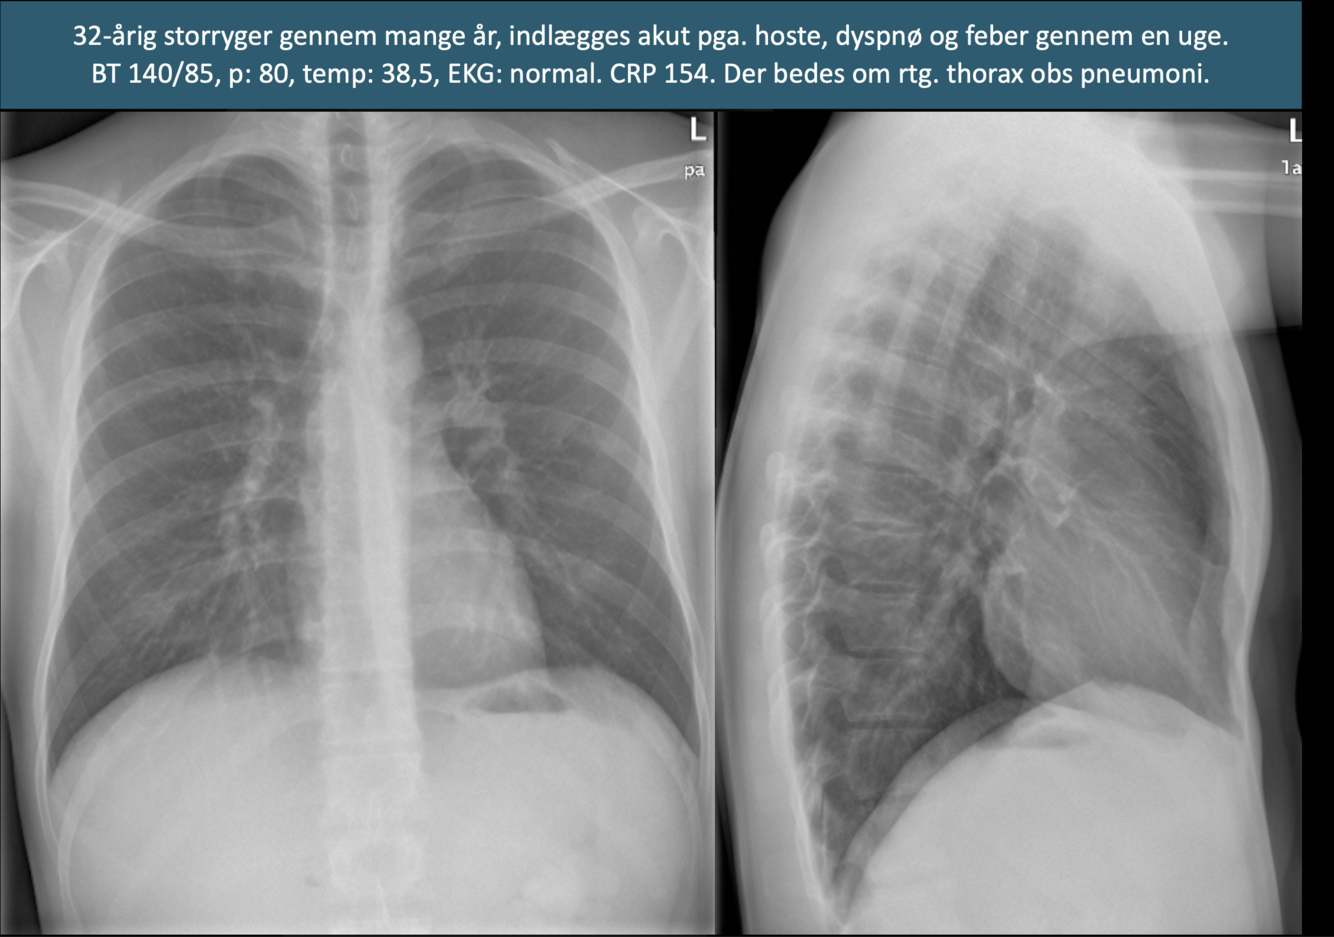

Q

Diagnose?

A

Hjertesvigt